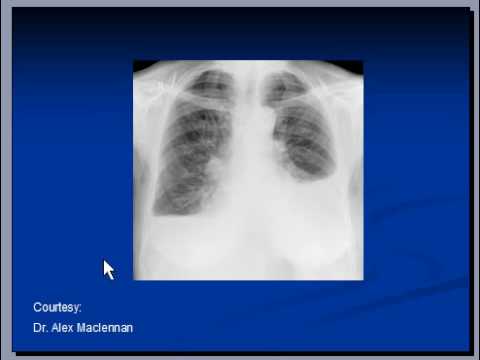

2. Cardiomegaly, OHA, Hypoglycemia 1. (...) Cardiomegaly's criteria on CXR: (...) Do remember that we can only measure CTR from CXR in PA erect.

4. Cardiomegaly. Case contributed by (...) A normal measurement should be less than 0.5. (...) Tag: cxr. Encyclopaedia. By Section: Anatomy; Approach; Classifications; Gamuts;

12. The cardiothoracic ratio aids in the detection of cardiomegaly, (...) The cardiothoracic ratio aids in the detection of cardiomegaly, (...) measurement, refs